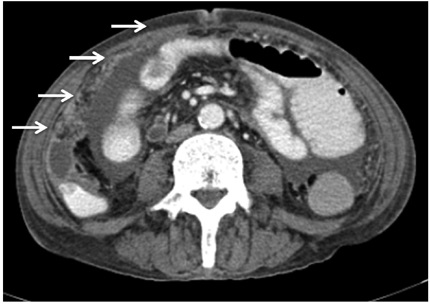

Al examen físico, como hallazgos positivos, se encontró abdomen levemente distendido, ruidos intestinales positivos, dolor a la palpación profunda de hipogastrio, sin irritación peritoneal; no se palpaban masas ni megalias. Los paraclínicos de ingreso no evidenciaron respuesta inflamatoria sistémica; la función renal se encontró alterada en relación a la nefropatía de base, en equilibrio hidroelectrolítico. El único hallazgo en el coprológico fue sangre oculta, por lo que fue llevado a colonoscopia, la cual reportó engrosamiento del pliegue a nivel de la ampolla ileocecal, pólipo en ciego de 2 cm de aspecto adenomatoso sésil, con base de implantación ancha. Se tomaron biopsias que fueron reportadas como adenoma tubular sin displasia de alto grado, y se complementó estudio con tomografía computarizada (TC) abdominal contrastado, que reportó dilatación del tercio medio del esófago, en relación a antecedente de esclerodermia, distensión de asas yeyunales proximales y engrosamiento de las válvulas conniventes, importante alteración de la grasa mesentérica y nodularidad del epiplón en toda su extensión, asociado a múltiples adenopatías con formación de pequeña colección hacia la fascia lateroconal (Figura 1).

Los hallazgos tomográficos incluyen engrosamiento liso y realce del peritoneo, mesenterio engrosado y nodular, ascitis de alta densidad (25-45 UH) y nódulos linfáticos de baja densidad (10). Sin embargo, en ausencia de factores de riesgo o hallazgos clínicos que alerten a la sospecha de TB, es imposible distinguirla de la carcinomatosis peritoneal, la cuál es su principal diagnóstico diferencial (11) y la enfermedad de Crohn, entre otros (12). Nuestro paciente se presentó con manifestaciones clínicas usuales de la tuberculosis abdominal, sin embargo no fue suficiente para tener en cuenta este diagnóstico de entrada. Más aún cuando tenemos de base síntomas B, sumados a un diagnóstico postoperatorio de carcinomatosis peritoneal; el reporte de ADA y la biopsia directa son las herramientas diagnósticas en nuestro paciente. Finalmente, el paciente no presentaba sintomatología respiratoria, sin embargo se documentó en él también TB pulmonar; la mayoría de los pacientes no tienen cuadros pulmonares asociados activos en el momento del diagnóstico, pero se conoce la asociación TB pulmonar y abdominal en el 20% de los pacientes sin coinfección con VIH (13).